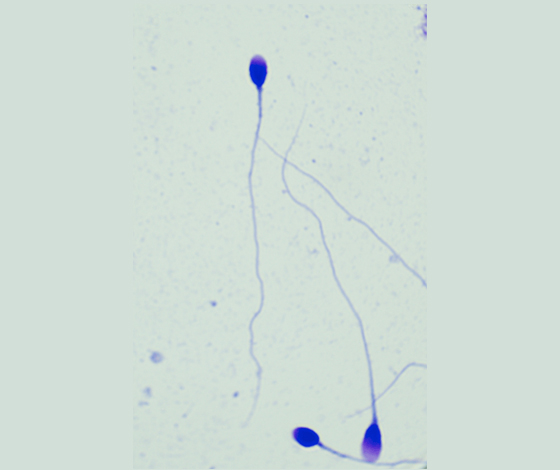

精子形態染色試劑盒(Diff-Quik法)

本產品用于精子形態染色。

精子形態學分析是評估精子質量的重要指標之一,精液中正常形態精子所占比例越低,可引起生育障礙。

檢驗原理:

采用世界衛生組織(WHO)推薦方法配制的精子形態快速染色液,對精子涂片進行染色,精子頂體區、體部、尾部呈現不同的著色,觀察正常精子的形態百分比。

染色結果示意圖: